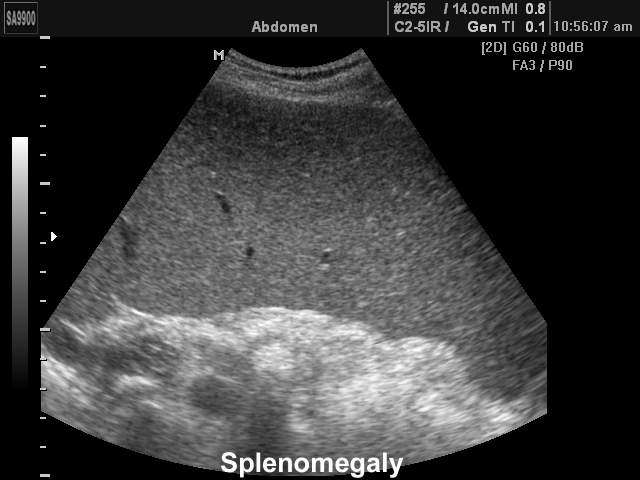

Спленомегалия

Спленомегалия при УЗИ